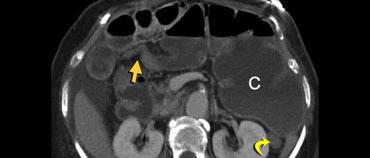

Đây là một bệnh nhân bị tắc ruột non.

Cuộn qua các hình ảnh.

Bạn có thể tìm thấy quai kín và nguyên nhân gây ra nó không?

Hình ảnh CT của tắc ruột non dạng quai kín phụ thuộc vào hai yếu tố:

- chiều dài đoạn ruột tạo thành quai kín

- hướng của quai ruột so với mặt phẳng tạo ảnh

Nếu quai kín ngắn và nằm trong mặt phẳng tạo ảnh, chúng ta sẽ thấy quai ruột hình chữ U hoặc chữ C.

Tắc ruột dạng quai kín với các quai ruột giãn xếp theo hình nan hoa. Có dày thành ruột và phù nề mạc treo gợi ý thiếu máu cục bộ

Một hình ảnh quan trọng khác của tắc ruột dạng quai kín là các quai ruột non giãn xếp theo hình nan hoa với các mạch máu mạc treo hội tụ về một điểm trung tâm.

Hình ảnh này hầu như luôn do xoắn ruột non gây ra.